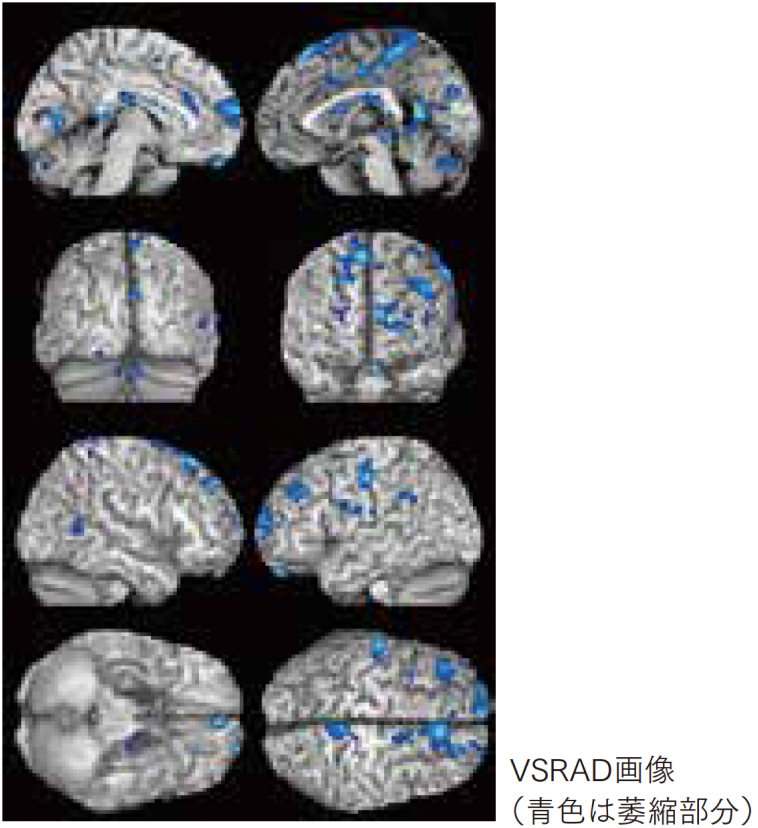

認知症検査「VSRAD」

宮崎:そこで当院では頭部MRI検査に「アルツハイマー型認知症診断システムVSRAD(ブイエスラド)」をオプションとして追加できるようにしています。

金山:アルツハイマー型認知症では、脳の中心に近い海馬傍回、扁桃、海馬の萎縮が起こることがわかっています。VSRADではそれらの部分の萎縮度を画像評価します。

宮崎:通常の頭部MRI撮影時間に加えて約5分程度長くなりますが、お体への負担もありません。

金山:この検査の結果は4段階の評価で示され、3以上の場合は脳に萎縮がみられる状態で、アルツハイマー型認知症の可能性が高いと言えます。検査対象は50歳以上の方です。